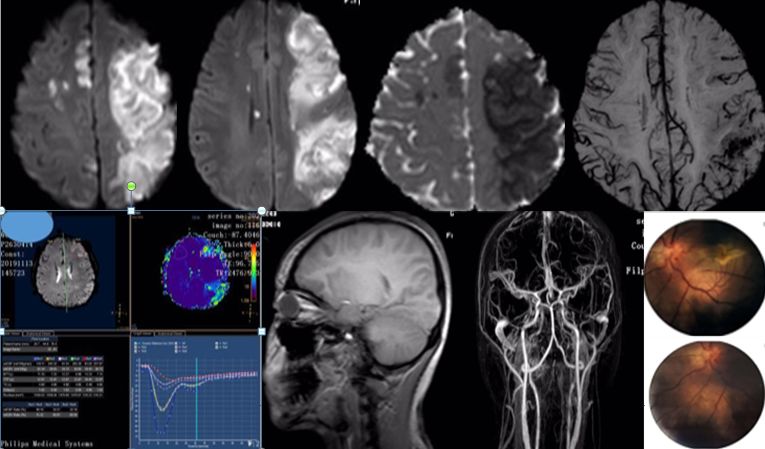

女,36岁,突发意识障碍伴抽搐。

答案:狼疮脑病合并可逆性后部白质脑病综合征(PRES)。补充病史:SLE病史。患者青年女性,有SLE病史,发作性神经系统症状,结合影像学考虑PRES。轻度PRES表现为皮质下或皮质下白质水肿,无实质出血、占位效应、或仅累及脑干或基底节中的一个。中度PRES表现为融合性水肿,从皮质向深部白质延伸,但不延伸至脑室边缘,小脑、脑干或基底节区中有两个轻度受累。重度PRES表现为从皮层到脑室的融合性水肿,或水肿或出血引起中线移位,小脑、脑干或基底节区均受累。

PRES本质上是一种可逆性的血管源性水肿,伴急性神经系统症状,如癫痫发作,脑病,头痛,视觉障碍等。常见原因为:高血压、肾衰竭、使用细胞毒*药性**物、自身免疫性疾病、子痫前期或子痫。约半数PRES患者既往有自身免疫性疾病,如:SLE、血栓性血小板减少性紫癜、甲减、硬皮病、Crohn病、溃疡性结肠炎、类风湿性关节炎、干燥综合征、结节性多动脉炎、肉芽肿性血管炎和视神经血管炎。PRES常由急剧的血压波动或细胞因子对血管壁的直接作用致内皮损伤,引起血脑屏障的破坏,继而引起脑水肿。对称性枕叶皮质下病变要和MELAS鉴别,二者形似神也似。MELAS 的MRI 表现为后部皮层信号改变、脑萎缩、基底节信号改变和钙化、脑白质营养不良。急性期通常会出现 T2 和 FLAIR 高信号,DWI 成像弥散受限。